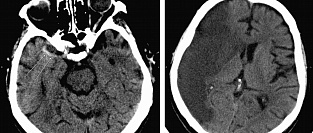

Компьютерная томография в прогнозировании риска инсульта у пациентов с ТИА

Все пациенты с микроинсультом или транзиторной ишемической атакой (ТИА) должны пройти компьютерную т...

07.12.2014 9431 #компьютерная томография #компьютерная томография головного мозга #транзиторная ишемическая атака #ТИА #инсульт #ишемический инсульт